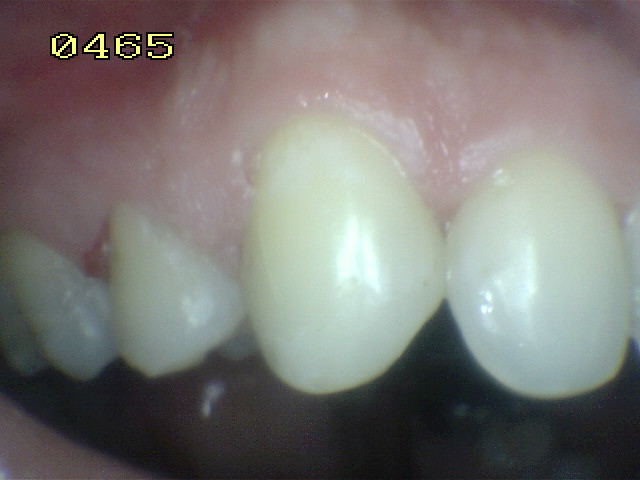

Clase III y VI

Eliminación de caries extensa en pieza dental anterior permanente con tratamiento de conducto realizado en consulta anterior, en paciente de sexo femenino de 30 años de edad.

Se observa caries  primaria en mesial  y en distal caries recurrente, con fractura del ángulo.

Vista desde vestibular donde se observa la caries mesial y distal con compromiso estético y funcional.

Aislación absoluta del campo operatorio con dique de goma y clamp cervical. se utiliza dique de goma oscura para mantener un buen contraste del campo operatorio.